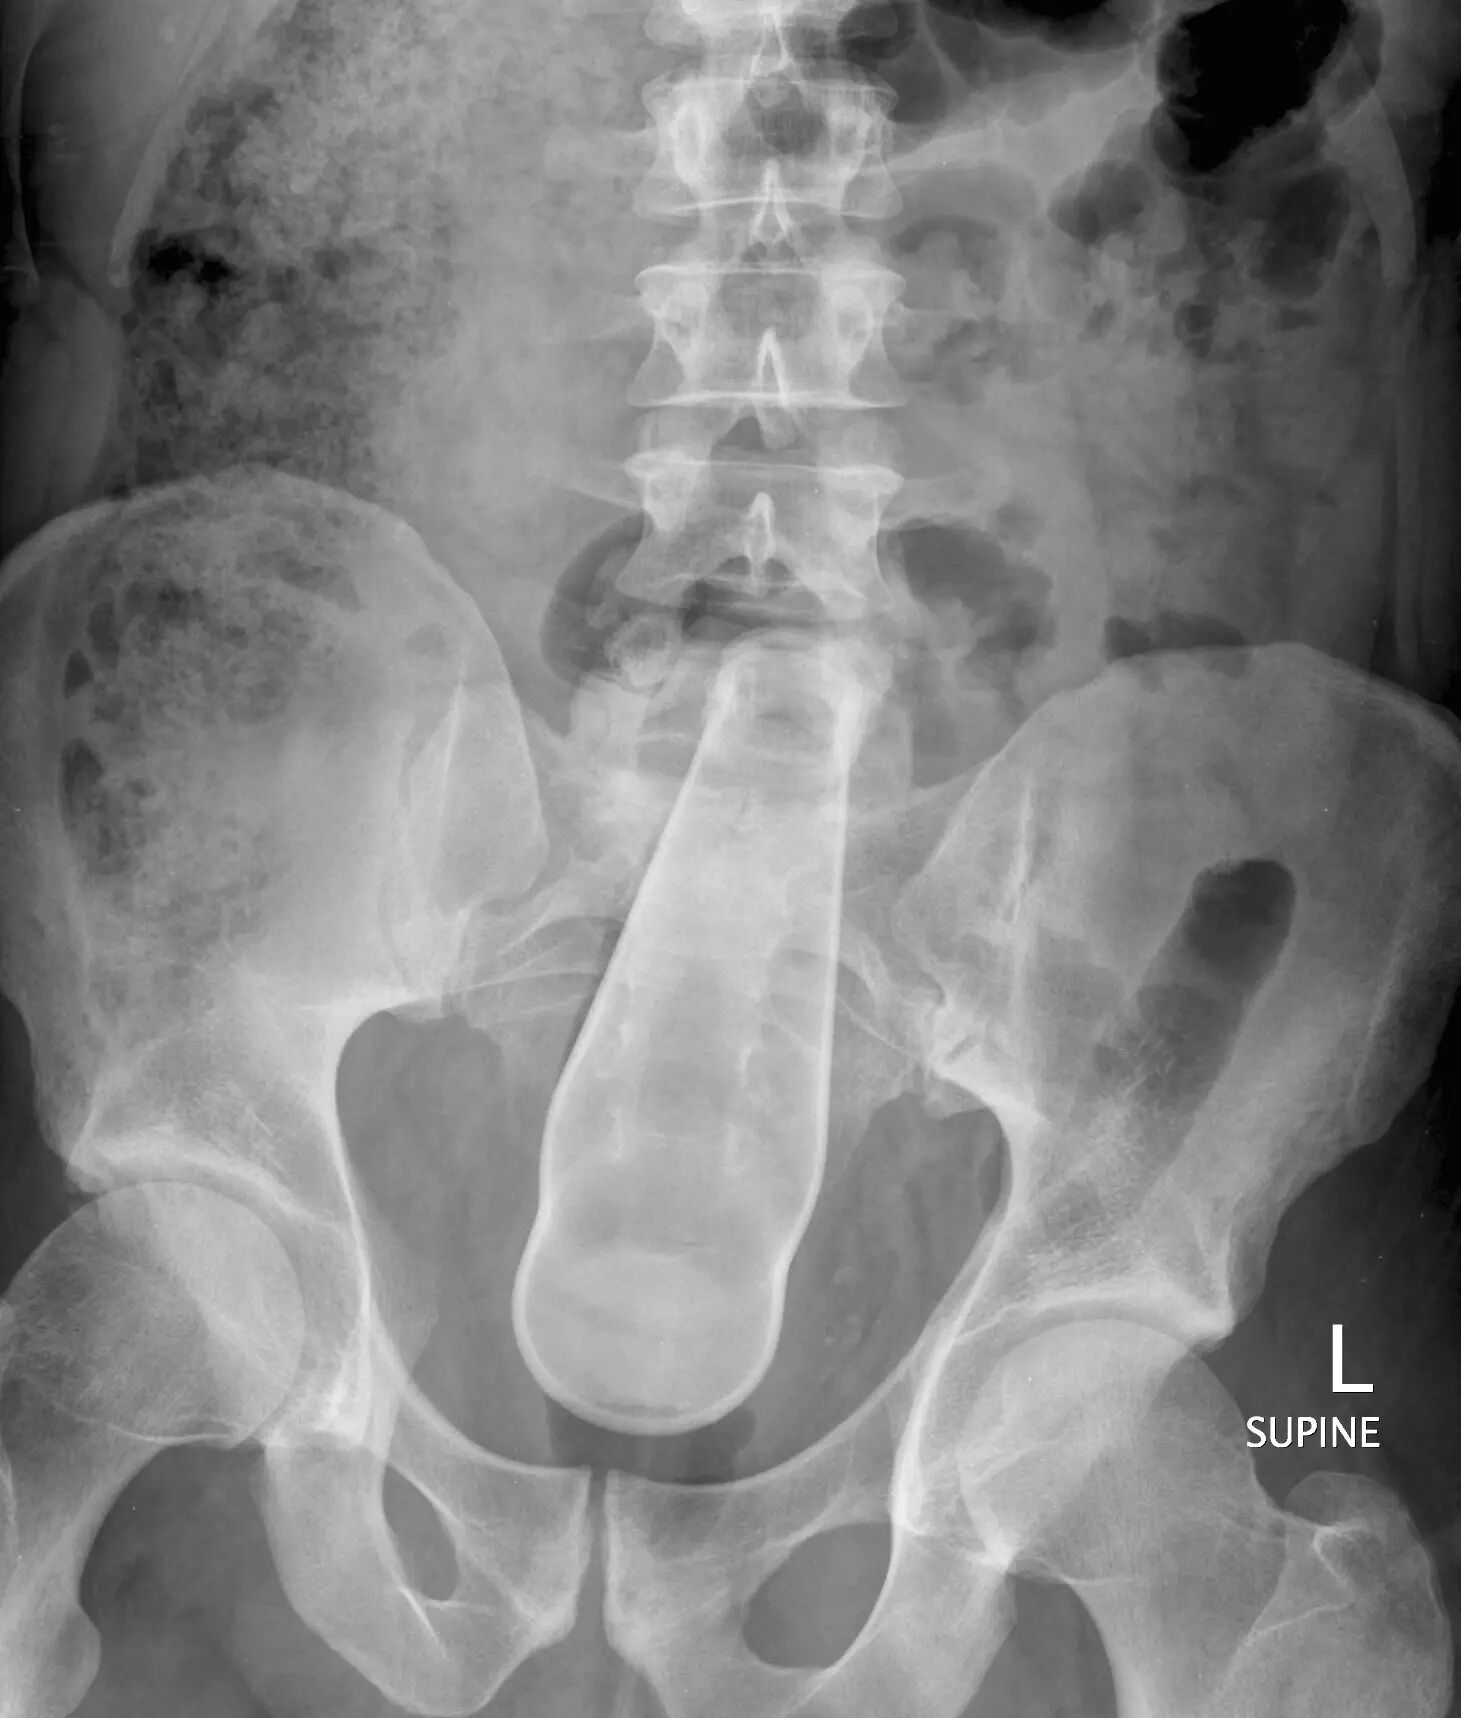

▲肛门内异物:饮料瓶

▲肛门内异物:假阴茎